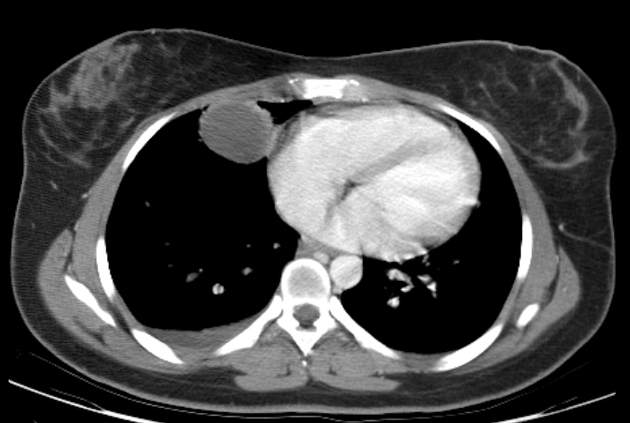

МСКТ при целомической кисте перикарда выявляет следующие анатомические признаки:

В режиме сканирования мягких тканей визуализируется округлое или овальное жидкостное образование с чёткими контурами, расположенное в переднем или нижнебоковом отделе средостения, прилегающим к перикарду.

В нативном режиме определяется однородная гиподенсивная структура кисты без включений, со средней плотностью, характерной для жидкого содержимого.

В режиме сканирования с контрастированием отсутствует накопление контрастного вещества в стенке образования, что подтверждает его неваскулярный характер и отсутствие признаков воспаления.

На мультипланарных реконструкциях прослеживается тонкая капсула образования, отсутствие инфильтрации окружающих тканей и смещение рядом расположенных структур — чаще лёгкого или сердца.